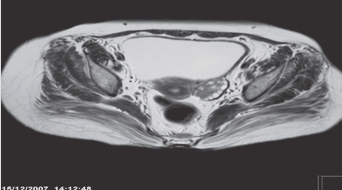

Polycystic ovary. Axial T2-weighted MRI

demonstrating a left ovary which is large in size and has multiple small cysts arranged around the periphery of the ovary, in a characteristic ‘string of pearls’ distribution